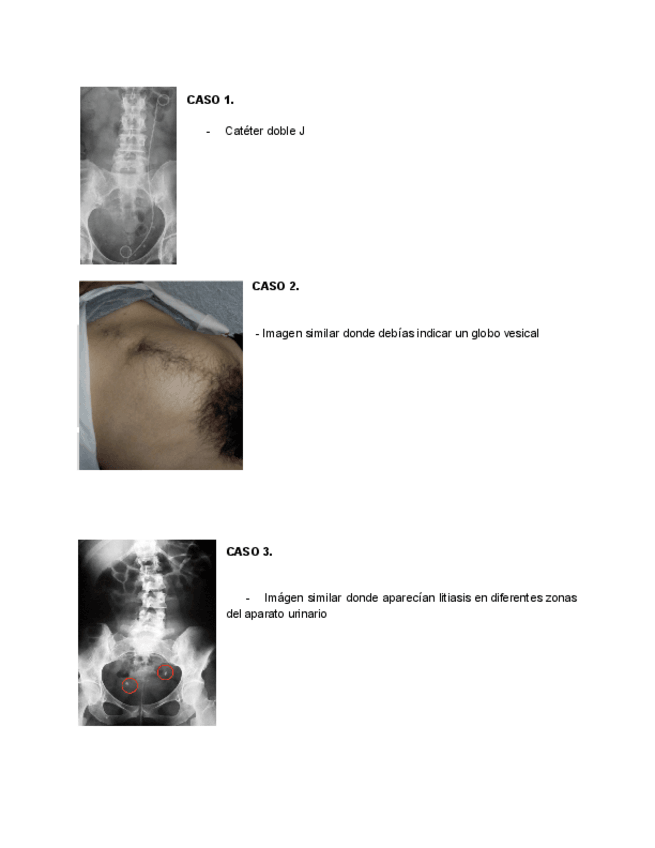

He publicado nuevos apuntes de 4º Nefrologia y Urología: Examen-practico-urologia-2025.pdf

3 páginas